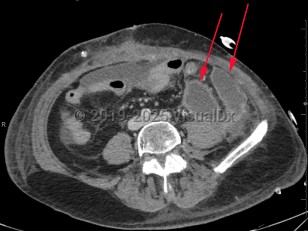

Intraabdominal abscess

The clinical presentation is varied and depends on the location of the abscess in the intraabdominal cavity. Vague abdominal discomfort is common, and pain may localize to a site of intraabdominal inflammation (in the patient with diverticulitis, for example). Fever and leukocytosis are also seen. The clinician should be mindful that patients who are immunosuppressed may have very mild and nonspecific symptoms. Patients who have a spinal cord injury or altered mental status may be similarly difficult to diagnose.

Patients who suffer from diverticulitis, inflammatory bowel disease (eg, ulcerative colitis, Crohn disease), or conditions that may lead to intestinal obstruction and subsequent perforation are at risk for intraabdominal abscesses. Also, patients who have penetrating trauma to the abdomen or undergo a surgical procedure involving intraabdominal or pelvic organs are at risk for this condition.